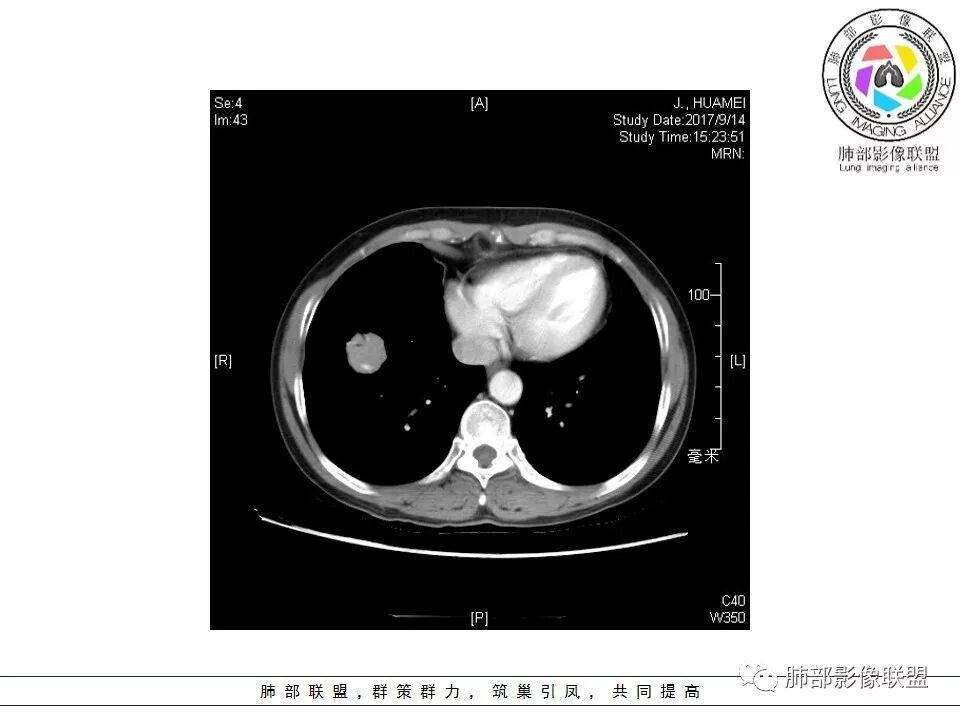

右肺下叶前基底段结节 边缘磨玻璃密度较清 内部支气管扩张,轻中度强化 穿行血管形态自然,支持淋巴瘤。

晨读,右肺下叶前基底段实性结节,边缘膨隆,可见多发浅分叶,结节内密度均匀,增强后呈轻度均匀强化,血管穿行走形自然,首先考虑恶性肿瘤,内有支气管穿行,淋巴瘤可能大,腺癌待排。

中年女性,体检发现,病史及化验无特殊。胸部CT右肺下叶前基底段见一类圆形结节,边界清楚,分叶不明显,边缘呈锯齿状改变,病灶内支气管穿行,无扩张及扭曲,增强扫描病灶明显均匀强化,内见穿行血管影,走形无扭曲。考虑粘膜相关性淋巴瘤可能。鉴别炎性假瘤、腺癌及小细胞癌。

胸CT:右肺下叶前基底段占位性病变,内可见支气管穿过,病灶边缘不规则,呈浅分叶,未见明显毛刺。纵隔窗可见病灶密度相对均匀,增强可见病灶强化,内可见血管增粗,边缘模糊,总体考虑恶性,腺?。良性疾病鉴别错构。

边缘彭隆,还是考虑肿瘤,支气管通入,肺内原发,支气管自然穿行稍扩张,血管比较自然同行,漂浮征,增强后整个比较均匀无明显坏死,淋巴瘤首选。恶性应该没有问题,建议穿刺。

内部支气管走形非常自然,达远端稍扩张;内部血管穿行也非常自然

内部密度比较均匀,我们一般来说,首先良性肿瘤不支持,因为它里面的血管走形太自然了;然后就是炎性病变跟恶性肿瘤,但是它的边缘膨隆比较厉害,有些地方还毛刺,不是很清楚,倾向一个恶性病变

恶性的血管穿行自然,包括支气管稍扩张,最常见还是淋巴瘤,它强化比较均匀;

粘液腺癌一般支气管扩张比较罕见,这个密度及强化太均匀,不是很符合,所以把淋巴瘤放前面,癌待排;